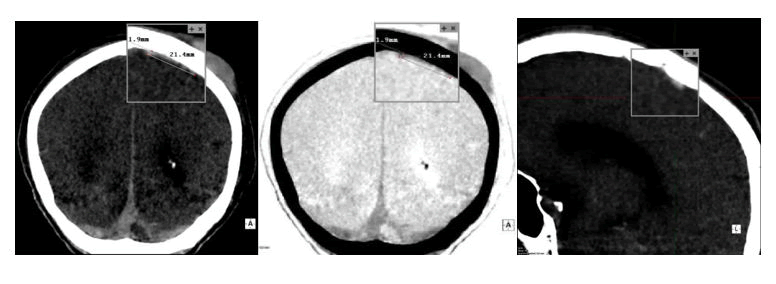

The presence of the same was then confirmed during the actual autopsy where it was possible to ascertain (Figure 2) how the reduced thickness actually made visualization difficult in traditional reconstructions.

Figure 2. (Left) Brain under examination in its entirety during the autopsy, a small hematoma is already visible in the right hemisphere. (Center) The same brain was cut along the coronal axis to investigate any other unknown hemorrhages. Here, the reduced thickness of the subdural hematoma can be observed. (Right) Hemorrhage and brain visualized from another perspective.